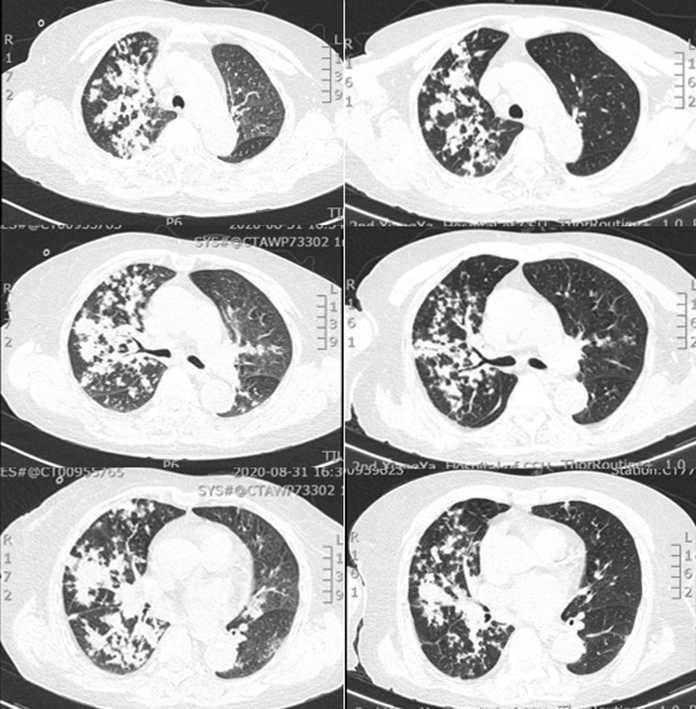

复查全腹部CT考虑不完全性肠梗阻及双肺感染,结合患者病史,考虑“外源性脂质性肺炎”可能性大。予以哌拉西林他唑巴坦抗感染,地塞米松抗炎,中药辅助治疗等;患者于8月20日左右出现发热,最高体温39.0℃,咳嗽咳痰症状较前加重,且伴有明显气促,无畏寒寒战,经治疗后仍有气促不适,为求进一步诊治,遂至我院门诊就诊,以“双肺病变查因”收住我科。起病以来,患者精神差,睡眠可,食欲减退,大便少,小便正常,体重未测。2020年8月13日于当地医院确诊为“不完全性肠梗阻、右肾囊肿”。余既往史无特殊。配偶2019年因肺结核去世。个人史、月经史、婚育史、家族史等均无特殊。体温36.5℃,脉搏82次/min,呼吸30次/min,血压100/57 mmHg。APACHE Ⅱ评分11分,SOFA评分2分,NRS-2002营养风险评分4分。急性面容,神清,精神较差,全身皮肤黏膜未见黄染,全身浅表淋巴结未触及肿大。胸廓无畸形,双侧呼吸动度对称,语颤无增强,双肺叩诊清音,双肺呼吸音粗,双肺可闻及干啰音,未闻及胸膜摩擦音。心率82次/min,律齐,各瓣膜听诊区未闻及病理性杂音。腹软,全腹无压痛及反跳痛,未触及腹部包块,肝、脾肋缘下未触及,腹部移动性浊音阴性,双肾区无叩击痛。肠鸣音正常。无杵状指(趾),双下肢不肿。2020年8月31日我院胸部CT示右肺弥漫性实变为主,伴渗出,左下肺亦有少许渗出(图3)。①双肺病变查因:外源性脂质性肺炎?Ⅰ型呼吸衰竭;②不完全性肠梗阻;③低蛋白血症;④低钠血症;⑤右肾囊肿。- 血气分析:pH 7.501,PaCO2 31.7 mmHg,PaO2 48.3 mmHg,Lac 0.9 mmol/L,HCO3- 25.9 mmol/L。

哌拉西林他唑巴坦4.5 g ivgtt q8h覆盖厌氧菌;细辛脑化痰;甲泼尼龙40 mg ivgtt qd(9月3-13日)、32 mg po qd(9月14日起)抗炎;泮托拉唑钠肠溶胶囊护胃,胰岛素降糖等治疗;9月4日转入普通病房,9月15日出院。治疗后患者右肺病灶较前明显吸收(图5)。出院前胸部X线片可见肺部病变较前明显好转(图6)。①外源性脂质性肺炎,Ⅰ型呼吸衰竭;②医院获得性肺炎;③糖尿病(分型未确定);④不完全性肠梗阻;⑤甲状腺肿大并结节;⑥低蛋白血症;⑦电解质紊乱;⑧右肾囊肿。出院后患者在当地医院住院20余天,激素每周减1片,复查胸部CT较前好转,但未完全吸收,后未再复查胸部CT。